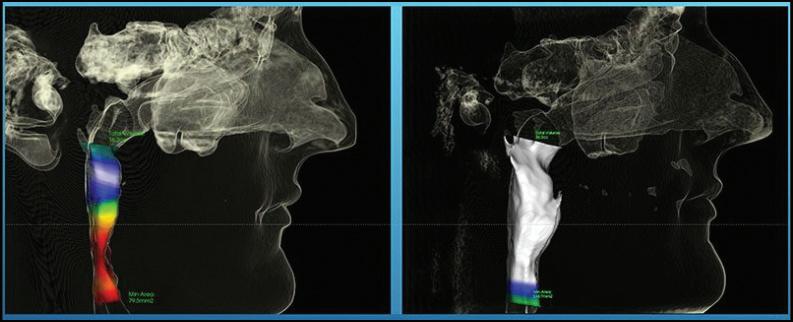

When a patient goes to their TMJ doctor, it is vitally important to make sure that certain technologies are used in order to get a good diagnosis and even greater treatment. In this article we will be looking at the merits of the dedicated Tesla coil, the x-rays to look at the jaw joints, the digital impression scanner, and the ever so important computer.

When it comes to getting a really great MRI of your TM joints, it is really important to be sure that the imaging center has a Tesla coil dedicated for this kind of work because it is so sensitive and can allow us to see the articular discs much better than some older technology. In too many cases, the MRI is done with an inferior machine and the reading is simply not that precise. This will often lead to a misdiagnosis and a path of treatment that costs lots of money, time, and frustration.

Another piece of technology in getting proper TMJ treatment involves the x-ray equipment. It is important first of all to go with “green” technology, i.e. low dose radiation and three-dimensional imaging. The 3-D imaging comes in really handy when the doctor wants to see what’s going on behind and around the corners of various bones, especially the condyle or jaw bone. This information helps when trying to correlate to the findings of the MRI; do the slipped discs make sense and is that why the jaw bone has shifted in that direction?

Airway before ALF Treatment; red shows very serious airway constriction.

Airway after ALF treatment, full resolution of this 30-year-old